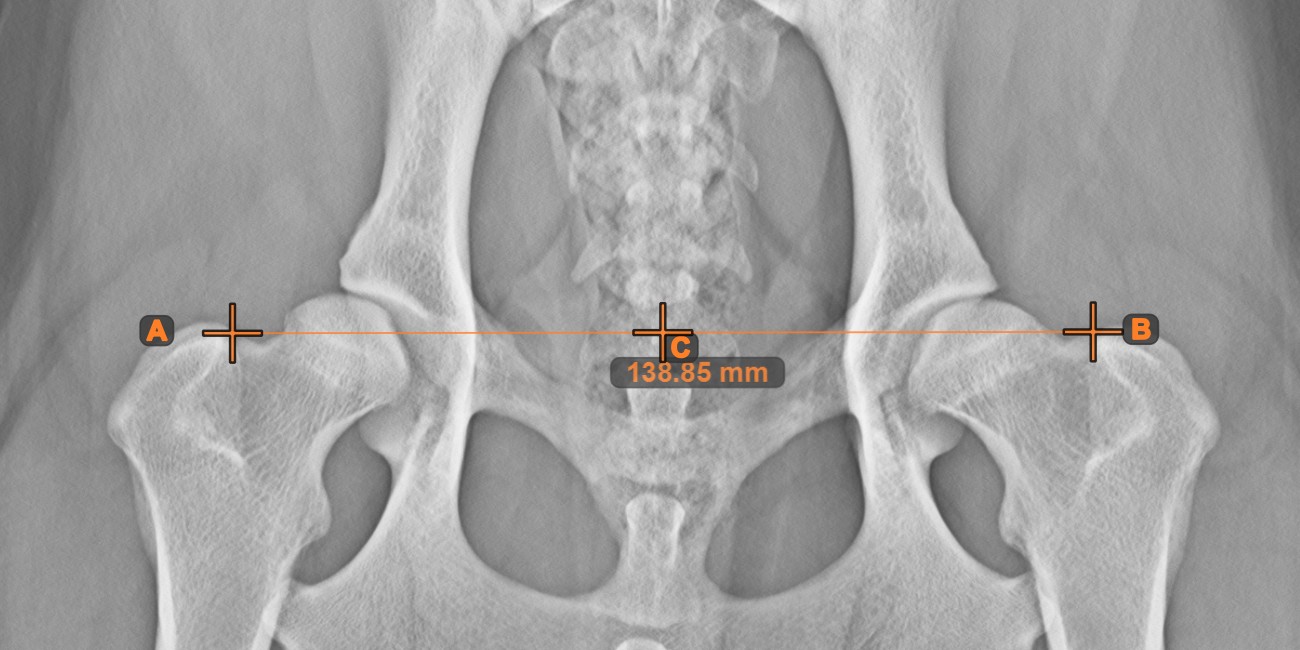

Mittlerer Punkt der Linie¶

Bestimmen und markieren Sie den Mittelpunkt einer neuen oder vorhandenen Linienmessung in der Szene mit dem Werkzeug Mittlerer Punkt der Linie

.

Wählen Sie das Werkzeug aus der linken Symbolleiste aus und weisen Sie es einer der verfügbaren Maustasten zu. Setzen Sie die Start- und Endpunkte in der Szene, wählen Sie sie aus bereits vorhandenen Punkten im Bild aus oder wählen Sie eine bereits gezeichnete Linie aus der Szene. Der Mittelpunkt der Linie wird automatisch berechnet und in der Szene platziert. Der Mittelpunkt jeder Linie wird stets mit dem Buchstaben C markiert.